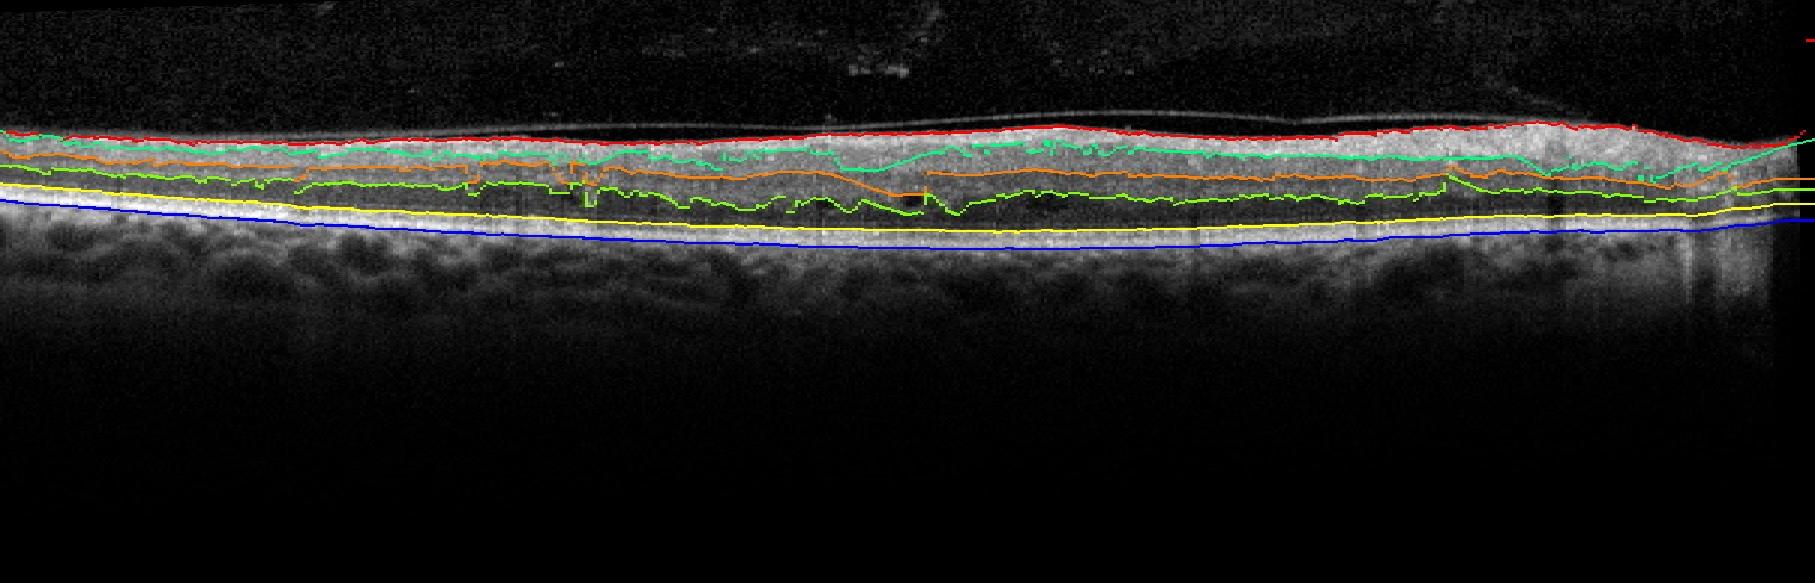

Since the error in Surface 2 is significantly high for abnormal OCT images using the proposed segmentation algorithm, the sub-retinal layer thicknesses on such abnormal images will be analyzed for the NFL and IPL layers combined (NFL++IPL, between Surface 1 and Surface 3), the INL, ONL and Outer layer (between Surface 5 and Surface 7). It is noteworthy, that although the performance of automated surface segmentation deteriorates on images with pathology, the proposed denoising and segmentation method has more reliable and repeatable performance for inner sub-retinal surface segmentation when compared to the OCTSEG system as shown in Fig. 7. The proposed method is capable of reliable estimation of the INL and ONL in image with cysts and sub-retinal disorganizations.

Figure 7: Comparative assessment of sub-retinal surface segmentation using the proposed method and the OCTSEG system on images with DME. Left column represents the automated segmentation produced by OCTSEG. Right column represents automated segmentation produced by the proposed method.